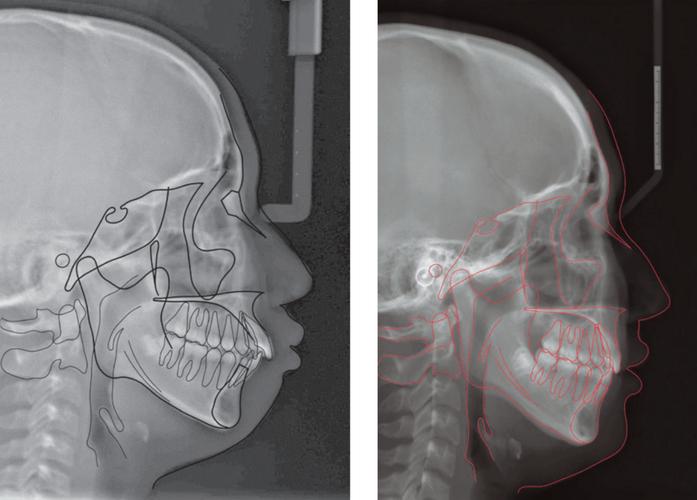

头颅侧位片的定位依赖于三个关键解剖点,它们共同定义了头颅的正中矢状面(Mid-sagittal Plane)和颅底平面(Cranial Base Plane):

- 鼻根点(Nasion, N): 鼻梁最凹陷点(鼻额缝中点)。

- 蝶鞍点(Sella, S): 蝶鞍的中心点(通常在侧位片上可见)。

- 耳点(Porion, Po): 外耳道最上点(外耳道穹窿顶)。

- 正中矢状面垂直于地面: 患者的头颅必须被摆放在一个位置,使得通过鼻根点(N)和蝶鞍点(S)的连线(NS线)与地面垂直,这意味着患者的头颅左右两侧完全对称地位于X光束中。

- 眶点(Orbitale, Or)与耳点(Po)水平对齐: 在侧位片上,眶点(Or,眼眶最下点)和耳点(Po)应位于同一水平线上,这确保了颅底平面(Frankfort Horizontal Plane, FH平面)在影像中是水平的。